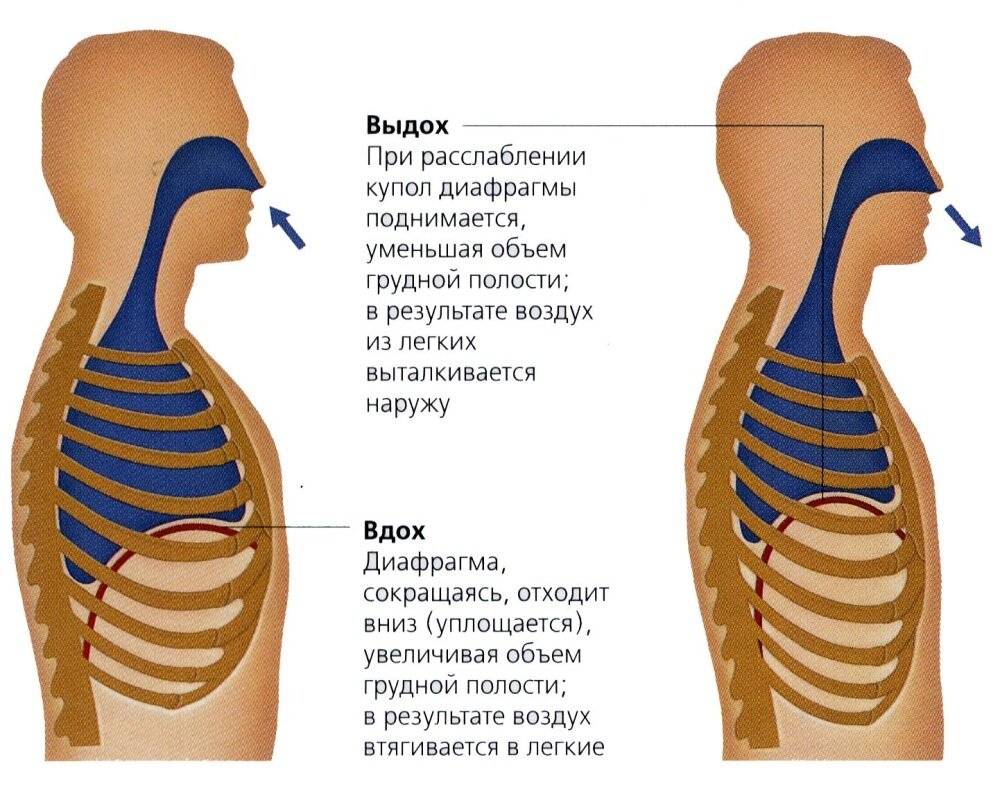

При любом типе дыхания за обработку кислорода отвечают легкие. Но их увеличение, как и изменение объема полости груди, зависит от 2 разных способов:

- При вдохе стенка груди приподнимается и отодвигается от позвоночника, из-за чего полость грудной клетки спереди увеличивается (образуется дополнительный объем между позвоночником и грудиной). В этом процессе участвуют ребра, прикрепленные к позвоночнику под острым углом. Своими концами они формируют дугу, расширяя возможный объем. Так как ребра крепятся к грудной кости, они тянут ее за собой.

- Второй способ зависит от опущения грудобрюшной преграды по направлению книзу. Это – диафрагма, имеющая куполообразную форму. Грудные мышцы отвечают в процессе дыхания за то, чтобы этот купол тянулся вниз, освобождая простор для легких. Середина опускается книзу и создается нужный объем. Из-за опущения грудная часть диафрагмы давит на живот, в результате выпячивается его стенка.

Главный орган в брюшном дыхании — диафрагма. Диафрагмальная мышца — это куполообразная перегородка, она отделяет грудную клетку от органов, расположенных ниже в брюшной полости. На вдохе диафрагмальная мышца идёт вниз и сжимается, заставляя брюшную стенку выдвигаться вперёд. В момент выдоха диафрагмальная мышца возвращается вверх и приобретает форму купола, выгоняя воздух из лёгких.

На вдохе диафрагма движется вниз, на выдохе — поднимается вверх

На вдохе диафрагма движется вниз, на выдохе — поднимается вверх